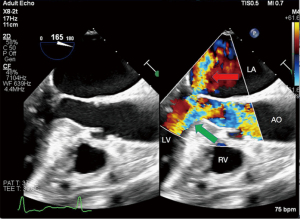

Twelve-lead electrocardiogram showed ST-T segment depression and signs of left ventricular hypertrophy. Transthoracic echocardiography (TTE) showed asymmetric septal hypertrophy with a maximal wall thickness of 16 mm at the LVOT level. Transesophageal echocardiography (TEE) revealed significant SAM of the anterior mitral leaflet (Figure 1, Video 1), causing dynamic LVOT obstruction (Figures 2,3) and severe MR (Figure 2, Video 2). On Valsalva maneuver, the LVOT pressure gradient reached 233 mmHg. Her left atrium was dilated and pulmonary artery systolic pressure was elevated. Reversed systolic wave was observed in the pulmonary vein flow (Figure 4). No abnormal muscle bundles were observed on imaging, including TEE and TTE.

To relieve MR and dynamic obstruction, the team opted for TEER with the MitraClip™ system. Pre-procedural TEE confirmed moderate to severe MR, a mitral valve effective regurgitant orifice area of 0.31 cm2, and a regurgitant volume of 78 mL. The mitral valve area was 3.1 cm2 (planimetrically measured in multiple views), with leaflet lengths of 24 mm (anterior) and 11 mm (posterior). The diastolic mean trans-mitral gradient was 1 mmHg. The regurgitant jet originated from the A2–P2 segment with reversed pulmonary vein flow.

Following implantation, TEE revealed significant improvement with only mild residual MR. The residual mitral valve orifice area was 1.6 cm2, and the mean diastolic trans-mitral pressure gradient increased to 4 mmHg. The LVOT gradient decreased to 81 mmHg. Invasive hemodynamic monitoring showed left atrial pressure dropped significantly from 55 mmHg pre-procedure to 25 mmHg post-procedure. Pulmonary vein flow spectrum normalized (Figure 5).

Immediately post-procedure, TEE demonstrated complete resolution of SAM and no evidence of device-induced LVOT obstruction. The implanted clip remained stable and was not displaced toward the LVOT, ruling out a significant Venturi effect.